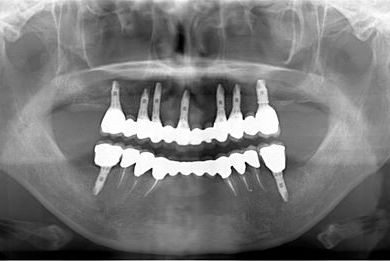

骨再生スピードインプラント治療+セラミック治療

| 性別/年齢 | 女性 / 43歳 | ||||||||||||||||||||||||||||||||

| 主訴 | 骨が薄いが、インプラント治療を希望。 | ||||||||||||||||||||||||||||||||

| 治療方針 | 抜歯と同時にインプラントを埋入し、治療期間を短縮する。ソケットリフトにて上顎洞を拳上し、インプラント治療を可能にする。 | ||||||||||||||||||||||||||||||||

| 治療内容 | インプラント9本(抜歯即日スピードインプラント、ソケットリフト、テンポラリーインプラント+仮歯)、メタルボンドセラミッククラウン18本、メタルボンドセラミックブリッジ6本(メタルボンド用土台6本)、遊離歯肉移植術 | ||||||||||||||||||||||||||||||||

| 総治療費 | 6,282,150円 | ||||||||||||||||||||||||||||||||

| 治療期間 | 1年8ヶ月 |